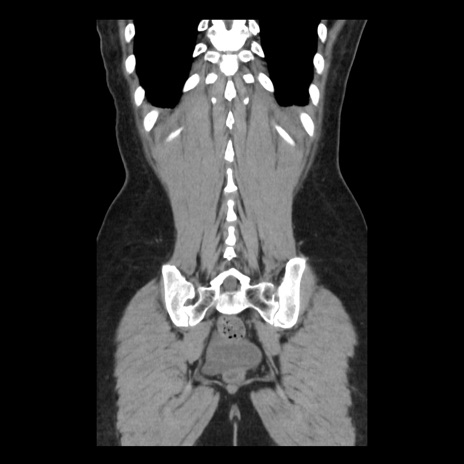

症例10(冠状断像)

【症例】 50歳代女性

【主訴】 腹痛

【現病歴】前日生レバーを食べた。今朝に排便あり。 昼前に突然発症の腹痛を生じ、当院救急外来を受診した。

【既往歴】 子宮筋腫にてで子宮全摘後

【身体所見】 意識清明、腹部:平坦、軟、下腹部やや左を中心に圧痛・反跳痛あり、筋性防御あり

【データ】WBC 7800、CRP 0.07